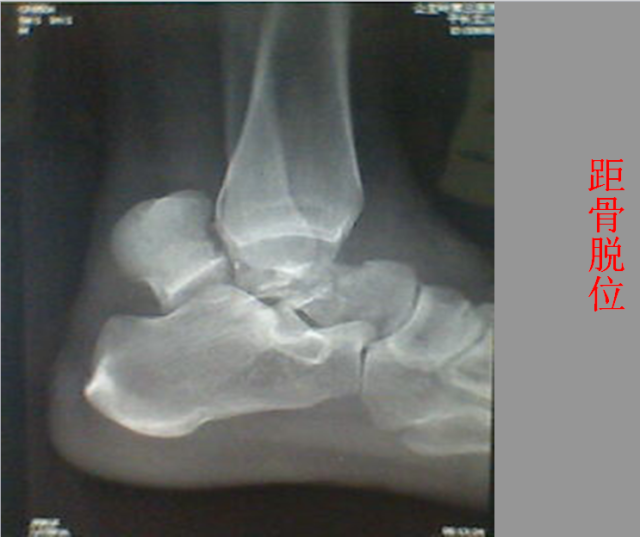

关节脱位篇

02

定义:关节脱位是暴力、关节感染、附近软组织挛缩或先天骨发育障碍造成的关节对位关系部分或完全脱离,即为半脱位或脱位。临床上以创伤性脱位*常见。